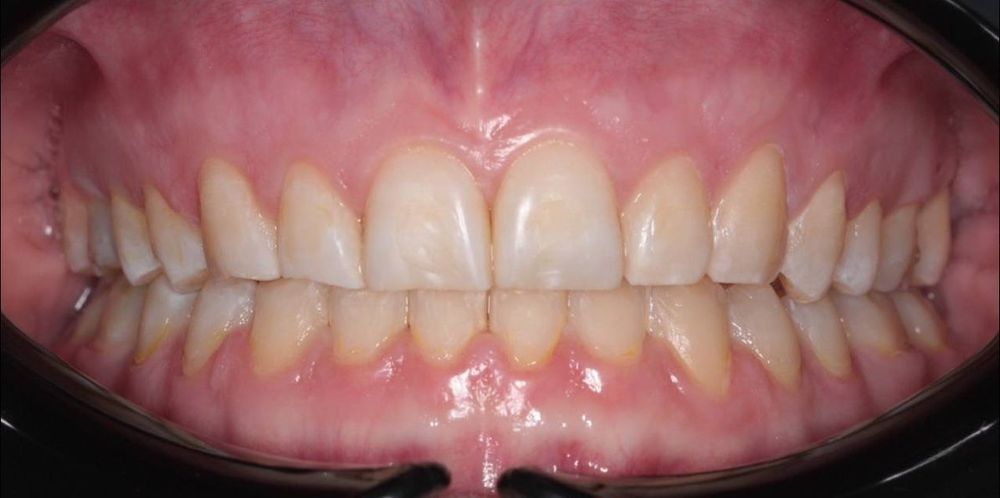

- глубокий прикус исправлен

- зубы выровнены, улыбка стала гармоничной и красивой

- восстановлено нормальное жевание и комфорт в суставе

- снижена стираемость эмали, улучшена функциональность всей зубочелюстной системы